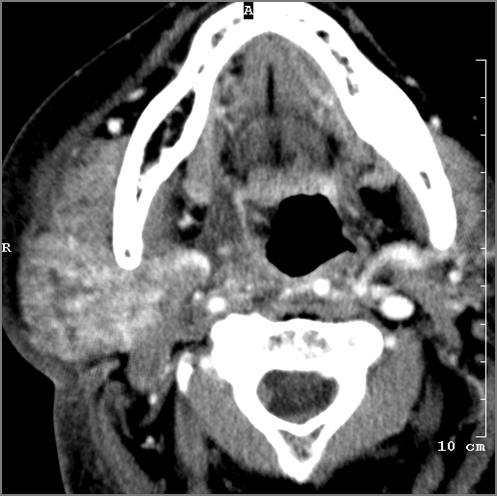

There is general or localized soft tissue swelling of the superficial or deep neck soft tissues.

There is gas in the soft tissues.

There is a foreign body separate from or in areas of soft tissue swelling.

There is excessive enhancement or thickening of the fat or other soft tissues within or surrounding the buccal space, masticator space, floor of the mouth, submandibular space or the adjacent superficial fascia or subcutaneous fat and skin.

There is subperiosteal abscess or an abscess cavity adjacent to or involving the maxilla or mandible.

There is endodontal or periodontal disease that might be causing cellulitis or abscess.

There is edema or abscess within the fat surrounding the parotid gland or of the adjacent masticator space or other spaces.

There is edema or abscess within the sublingual or submandibular space.